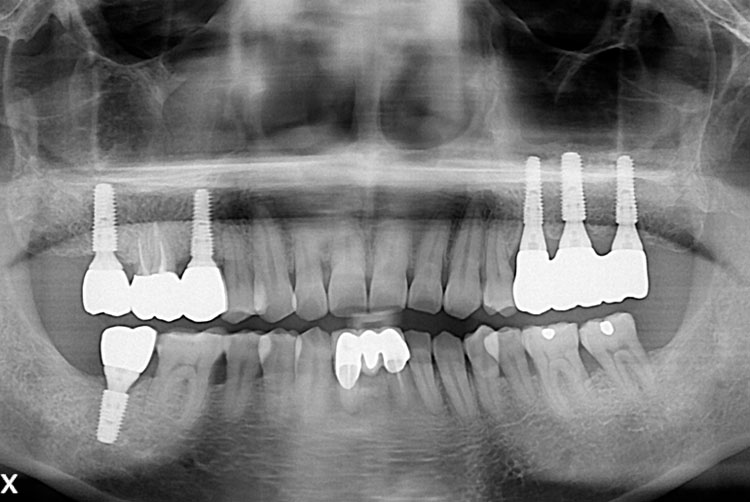

[임플란트] 임플란트

치료후 : 2018-08-29

세종치과는 많은 환자와 다양한 케이스를 바탕으로 항상 편안한 임플란트 수술을 제공하고자 노력하고,

오래동안 튼튼히 쓸 수 있는 임플란트 수술을 가장 큰 목표로 삼고 있습니다.